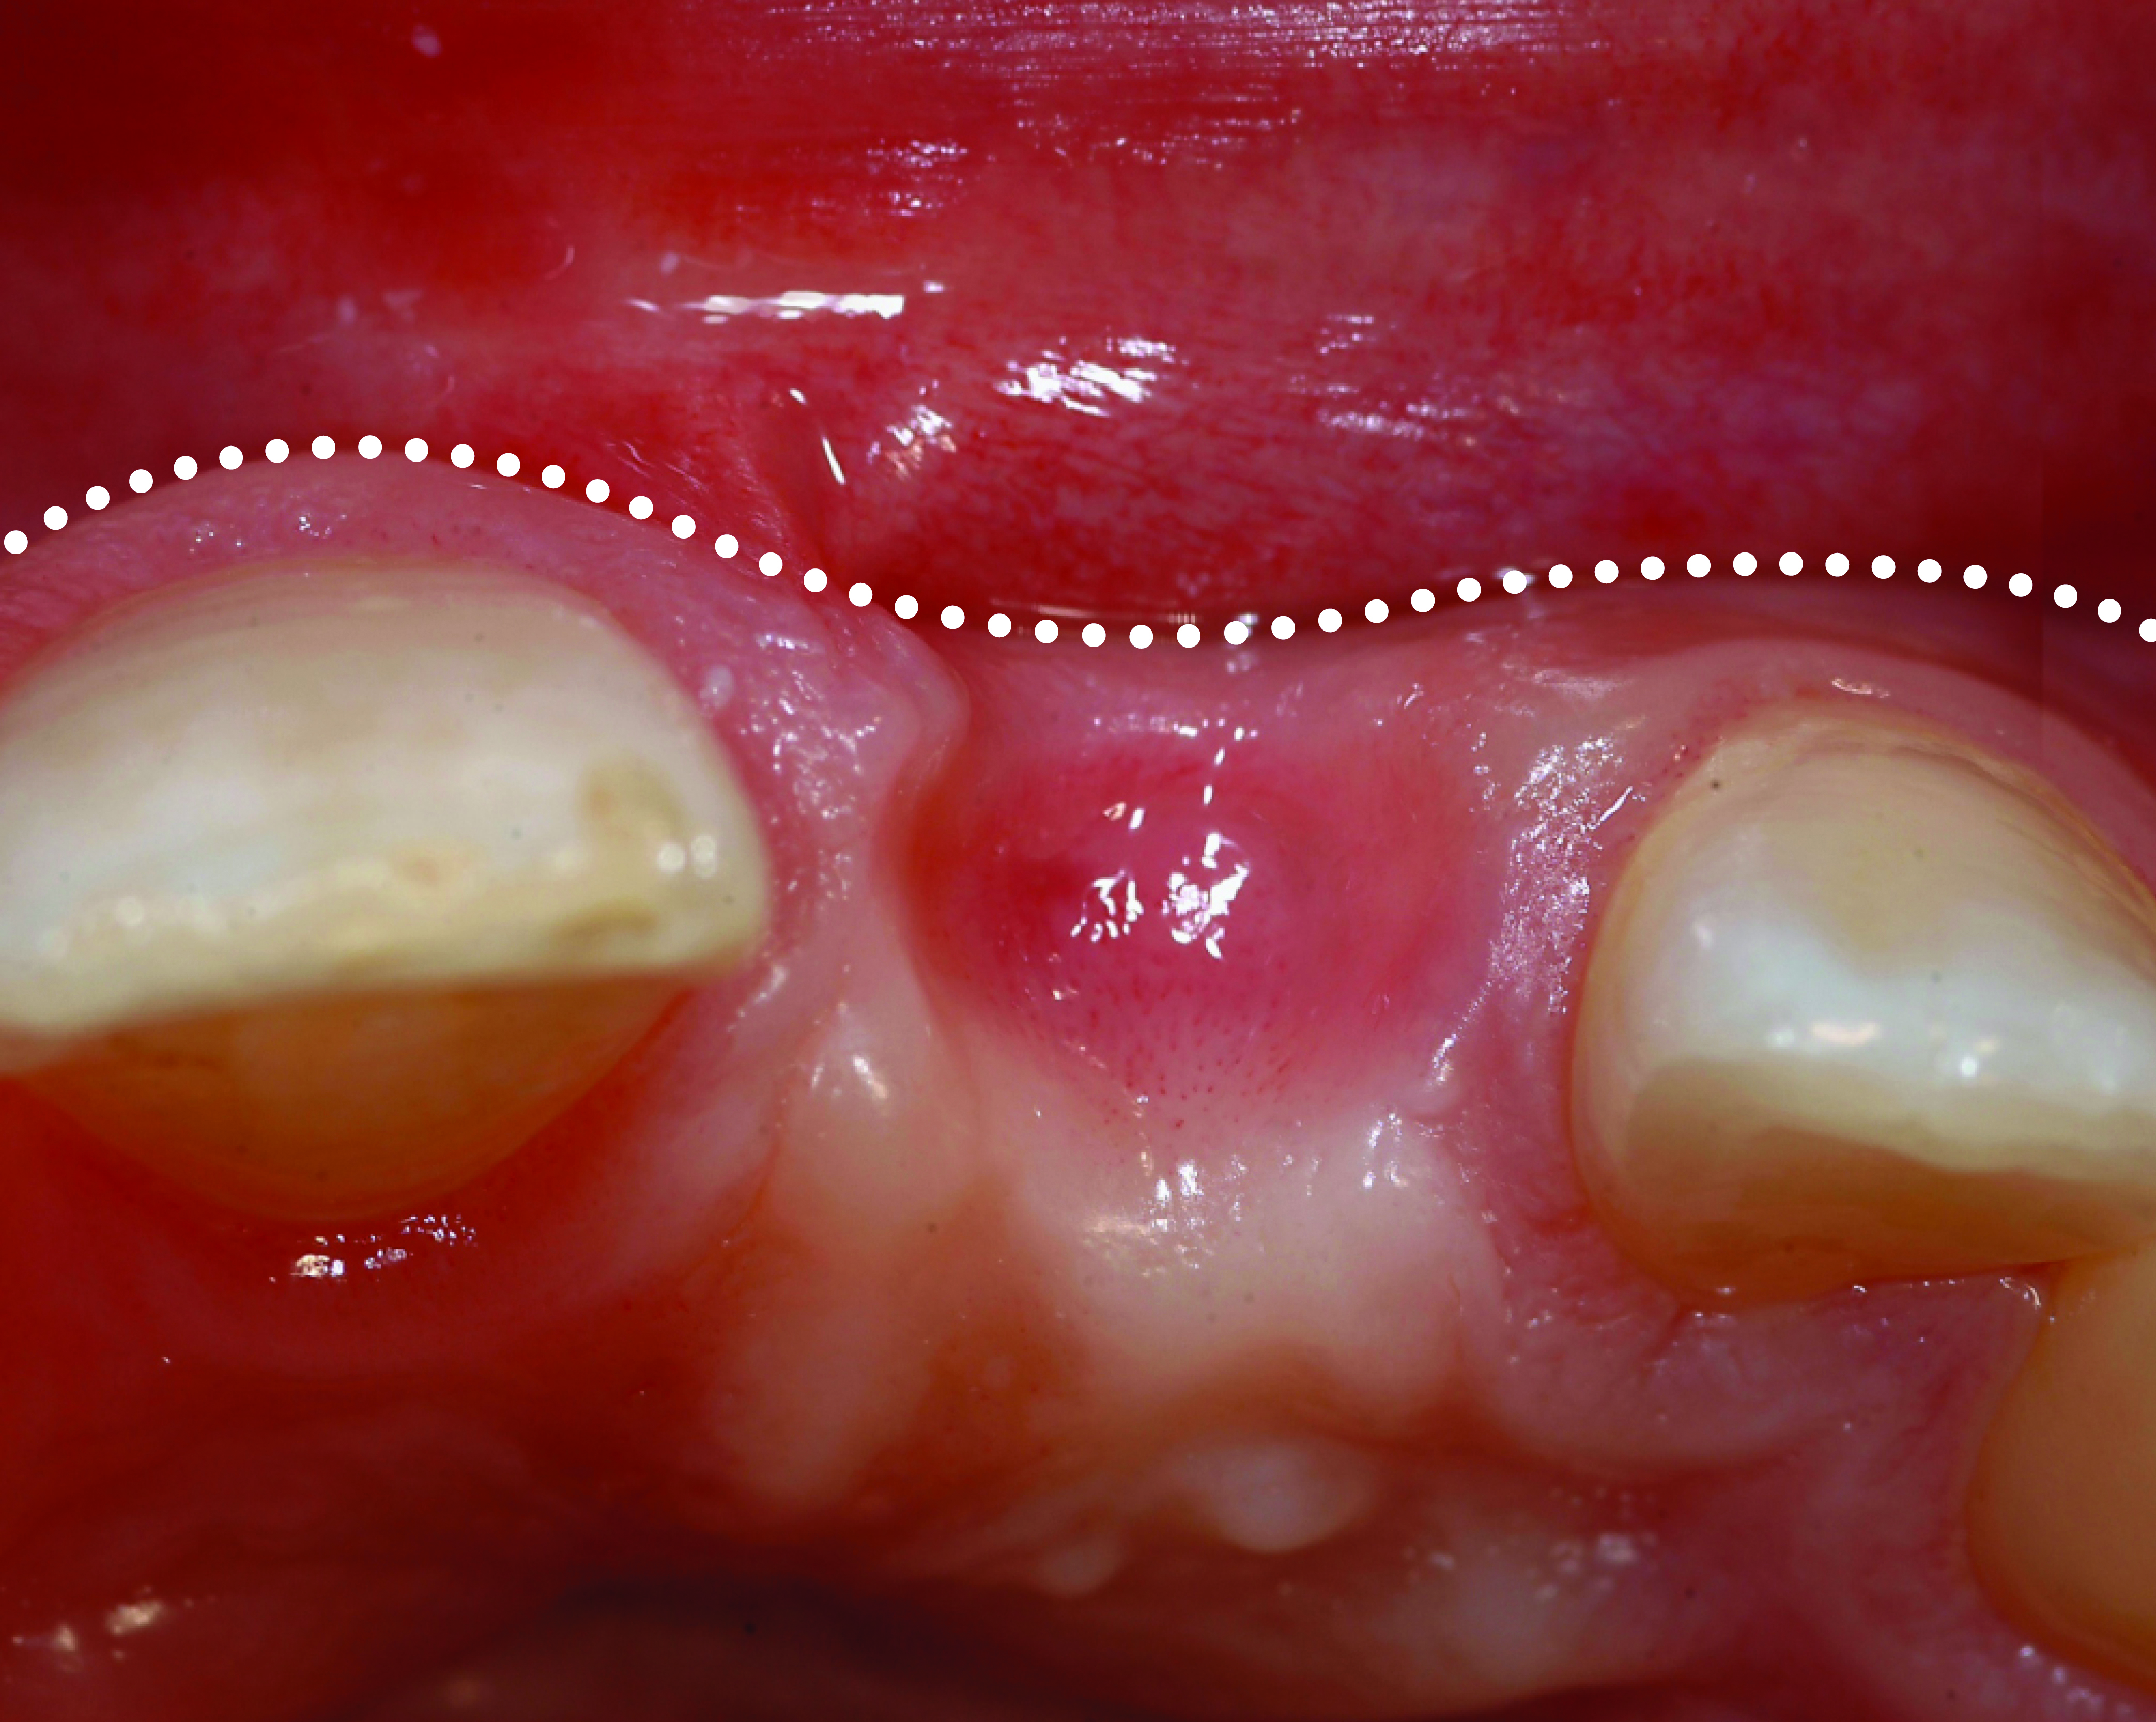

Fig 17. Preoperative view of the fractured No. 9.

Figure 17

Similarly, the approach of immediate implant placement and restoration is increasingly being used by clinicians, although the esthetic risks are considered high by some, because the procedure requires precision and careful management of hard and soft tissues. Aside from the patient-driven rationale for this approach, in appropriately selected cases, tissue guidance by the fixed restoration may lead to enhanced papilla development and better post-restoration facial tissue stability, because the soft tissues are less likely to slump or lose their anatomy. De Rouck and coauthors reported enhanced results with immediate versus delayed implant restoration.21 The case illustrated in Figure 17 involved extraction of tooth No. 9 and immediate implant placement, placement of a xenograft material in the residual horizontal defect, and fabrication/delivery of a provisional restoration. Implant placement at the time of tooth extraction may not prevent ridge resorption from occurring, but management of the residual horizontal defect between the socket wall and implant surface can influence the tissue level, particularly on the facial aspect.22 It is the authors’ observation that specific treatment with an anorganic bone graft (xenograft) can reduce buccal ridge resorption, and as a consequence, will positively influence the facial soft-tissue levels.